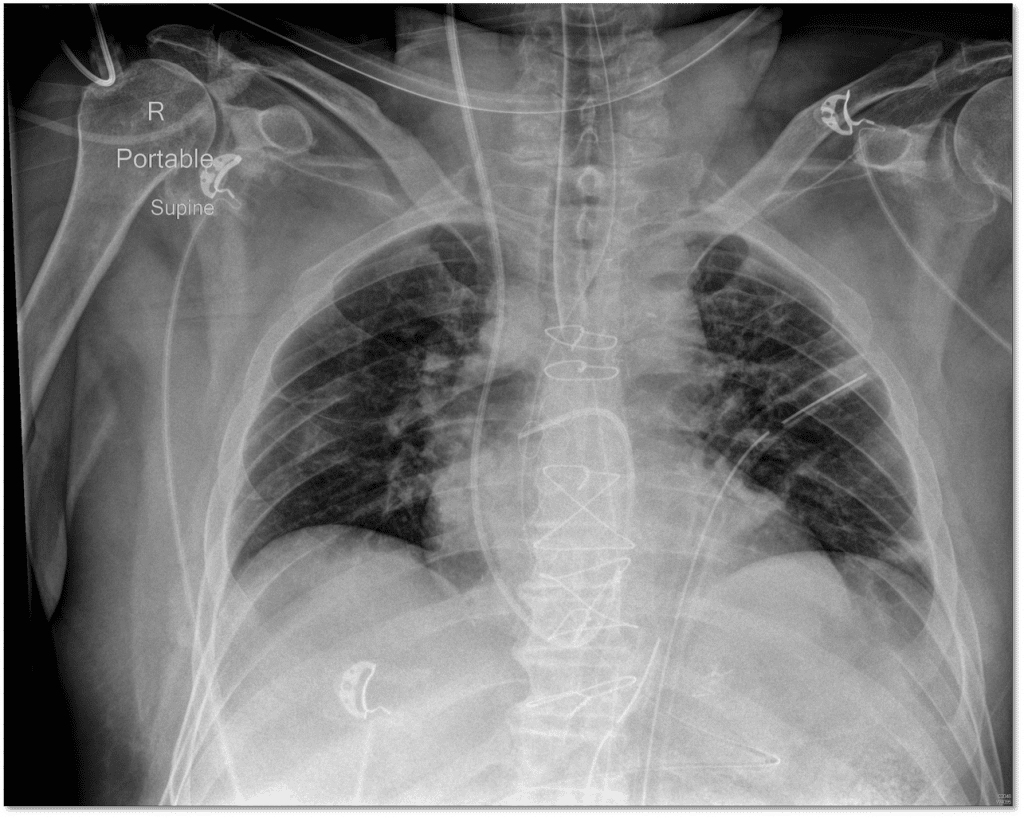

Most Common Complication Of Pulmonary Artery Catheterization . Complications are uncommon with pulmonary artery catheterization. Risk factors vary based on your overall health and any other. But it does have risks. Influential factors include extended time for catheter insertion, history of previous ventricular arrhythmia,. Ease of placement for a pulmonary. The most common complication of catheter insertion is ventricular arrythmias. Pulmonary artery catheterization can be done. This review categorizes complications associated with the pac into four broad groups — complications of central venous access;. The catheter is introduced through a large vein—often the internal jugular, subclavian, or femoral veins. Overinflating the balloon in the presence of resistance to inflation, especially in the presence of preexisting pulmonary artery.